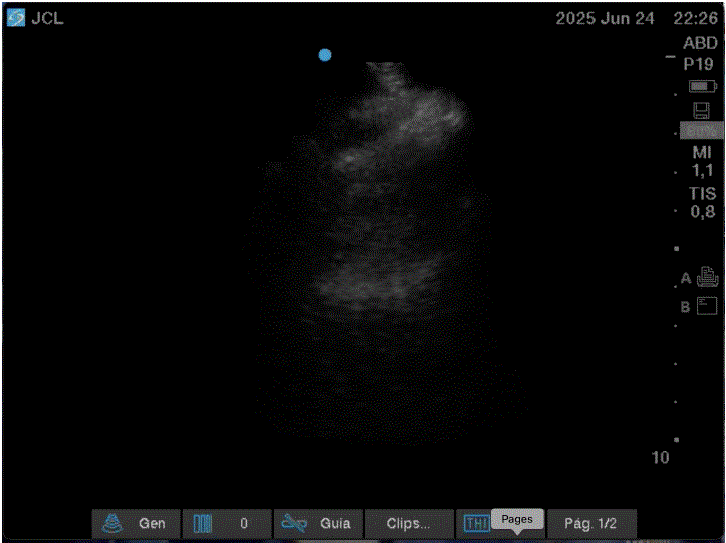

In the clinical case presented, the complete pneumothorax corresponds as defined by Kyoung MR, et al [12]. and will also lead to lung collapse causing total atelectasis. Let us remember that this atelectasis pathophysiologically occurs due to the absence of peripheral expansion of the lung and will be expressed in the x-ray study once all the trapped gas that occurs in the alveolar exchange has been absorbed, which begins when this exchange mechanism is stopped [13]. Due to this, in the images obtained ultrasound in the case, the lung can be seen as a collapsed mass in which a static or absent bronchogram is observed. The visceral pleura will not be in contact with the visceral pleura or will be too far medial that pleural sliding cannot be detected in the ultrasound image. It should not be strange, as in this case, in patients with total collapse of the lung, that the identification of this point called by the authors as “atelectatic point” could be a support point equivalent to the “lung point”, which could not be visualized, once identifying in the anterior zones the signs that reflect the loss of contact between the visceral and parietal pleura, and identifying in the region of the posterior axillary line the atelectatic lung, which is located in the anterolateral and inferior quadrants of the thorax [14], with the dynamic respiratory changes that make the image of a collapsed lung appear upon contact with the thoracic wall during expiration (Image A) and disappear with inspiration generating the typical image that is seen in pneumothorax (Image B). This finding is undoubtedly repeat over and over again with ventilatory dynamics, allowing us to assess its reproducibility in the case of complete pneumothorax, where an atelectatic lung will always coexist. This is a sign that we believe may have diagnostic value for complete pneumothorax. The images obtained were correlated with the simple CT scan performed on the patient as part of his comprehensive workup protocol (Image C).

Image B: Patient in inspiration in which we observe the loss of pulmonary parenchyma, without sliding of the pleural line and without artifacts, as well as the absence of the lung pulse, characteristic of pneumothorax in the ultrasound.